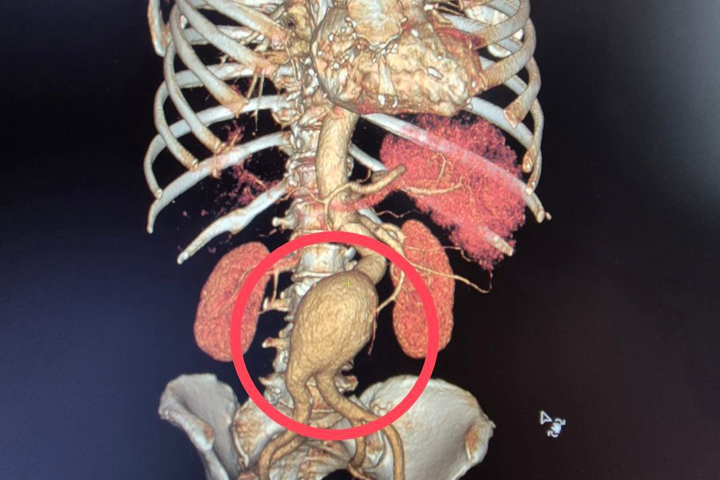

Как пояснили медики, к ним поступила 60-летняя пациентка с крайне опасным диагнозом — мешотчатая аневризма брюшной аорты.

«Это патологическое расширение главного сосуда организма, которое в любой момент может привести к внутреннему кровотечению. Случай действительно уникальный — аневризма брюшной аорты считается «бомбой замедленного действия», а мешотчатая форма особенно опасна из-за риска мгновенного разрыва.

Операцией руководил заведующий отделением сосудистой хирургии БГКБ Андрей Ковалев, она продлилась более шести часов и прошла успешно. Угроза жизни отступила.